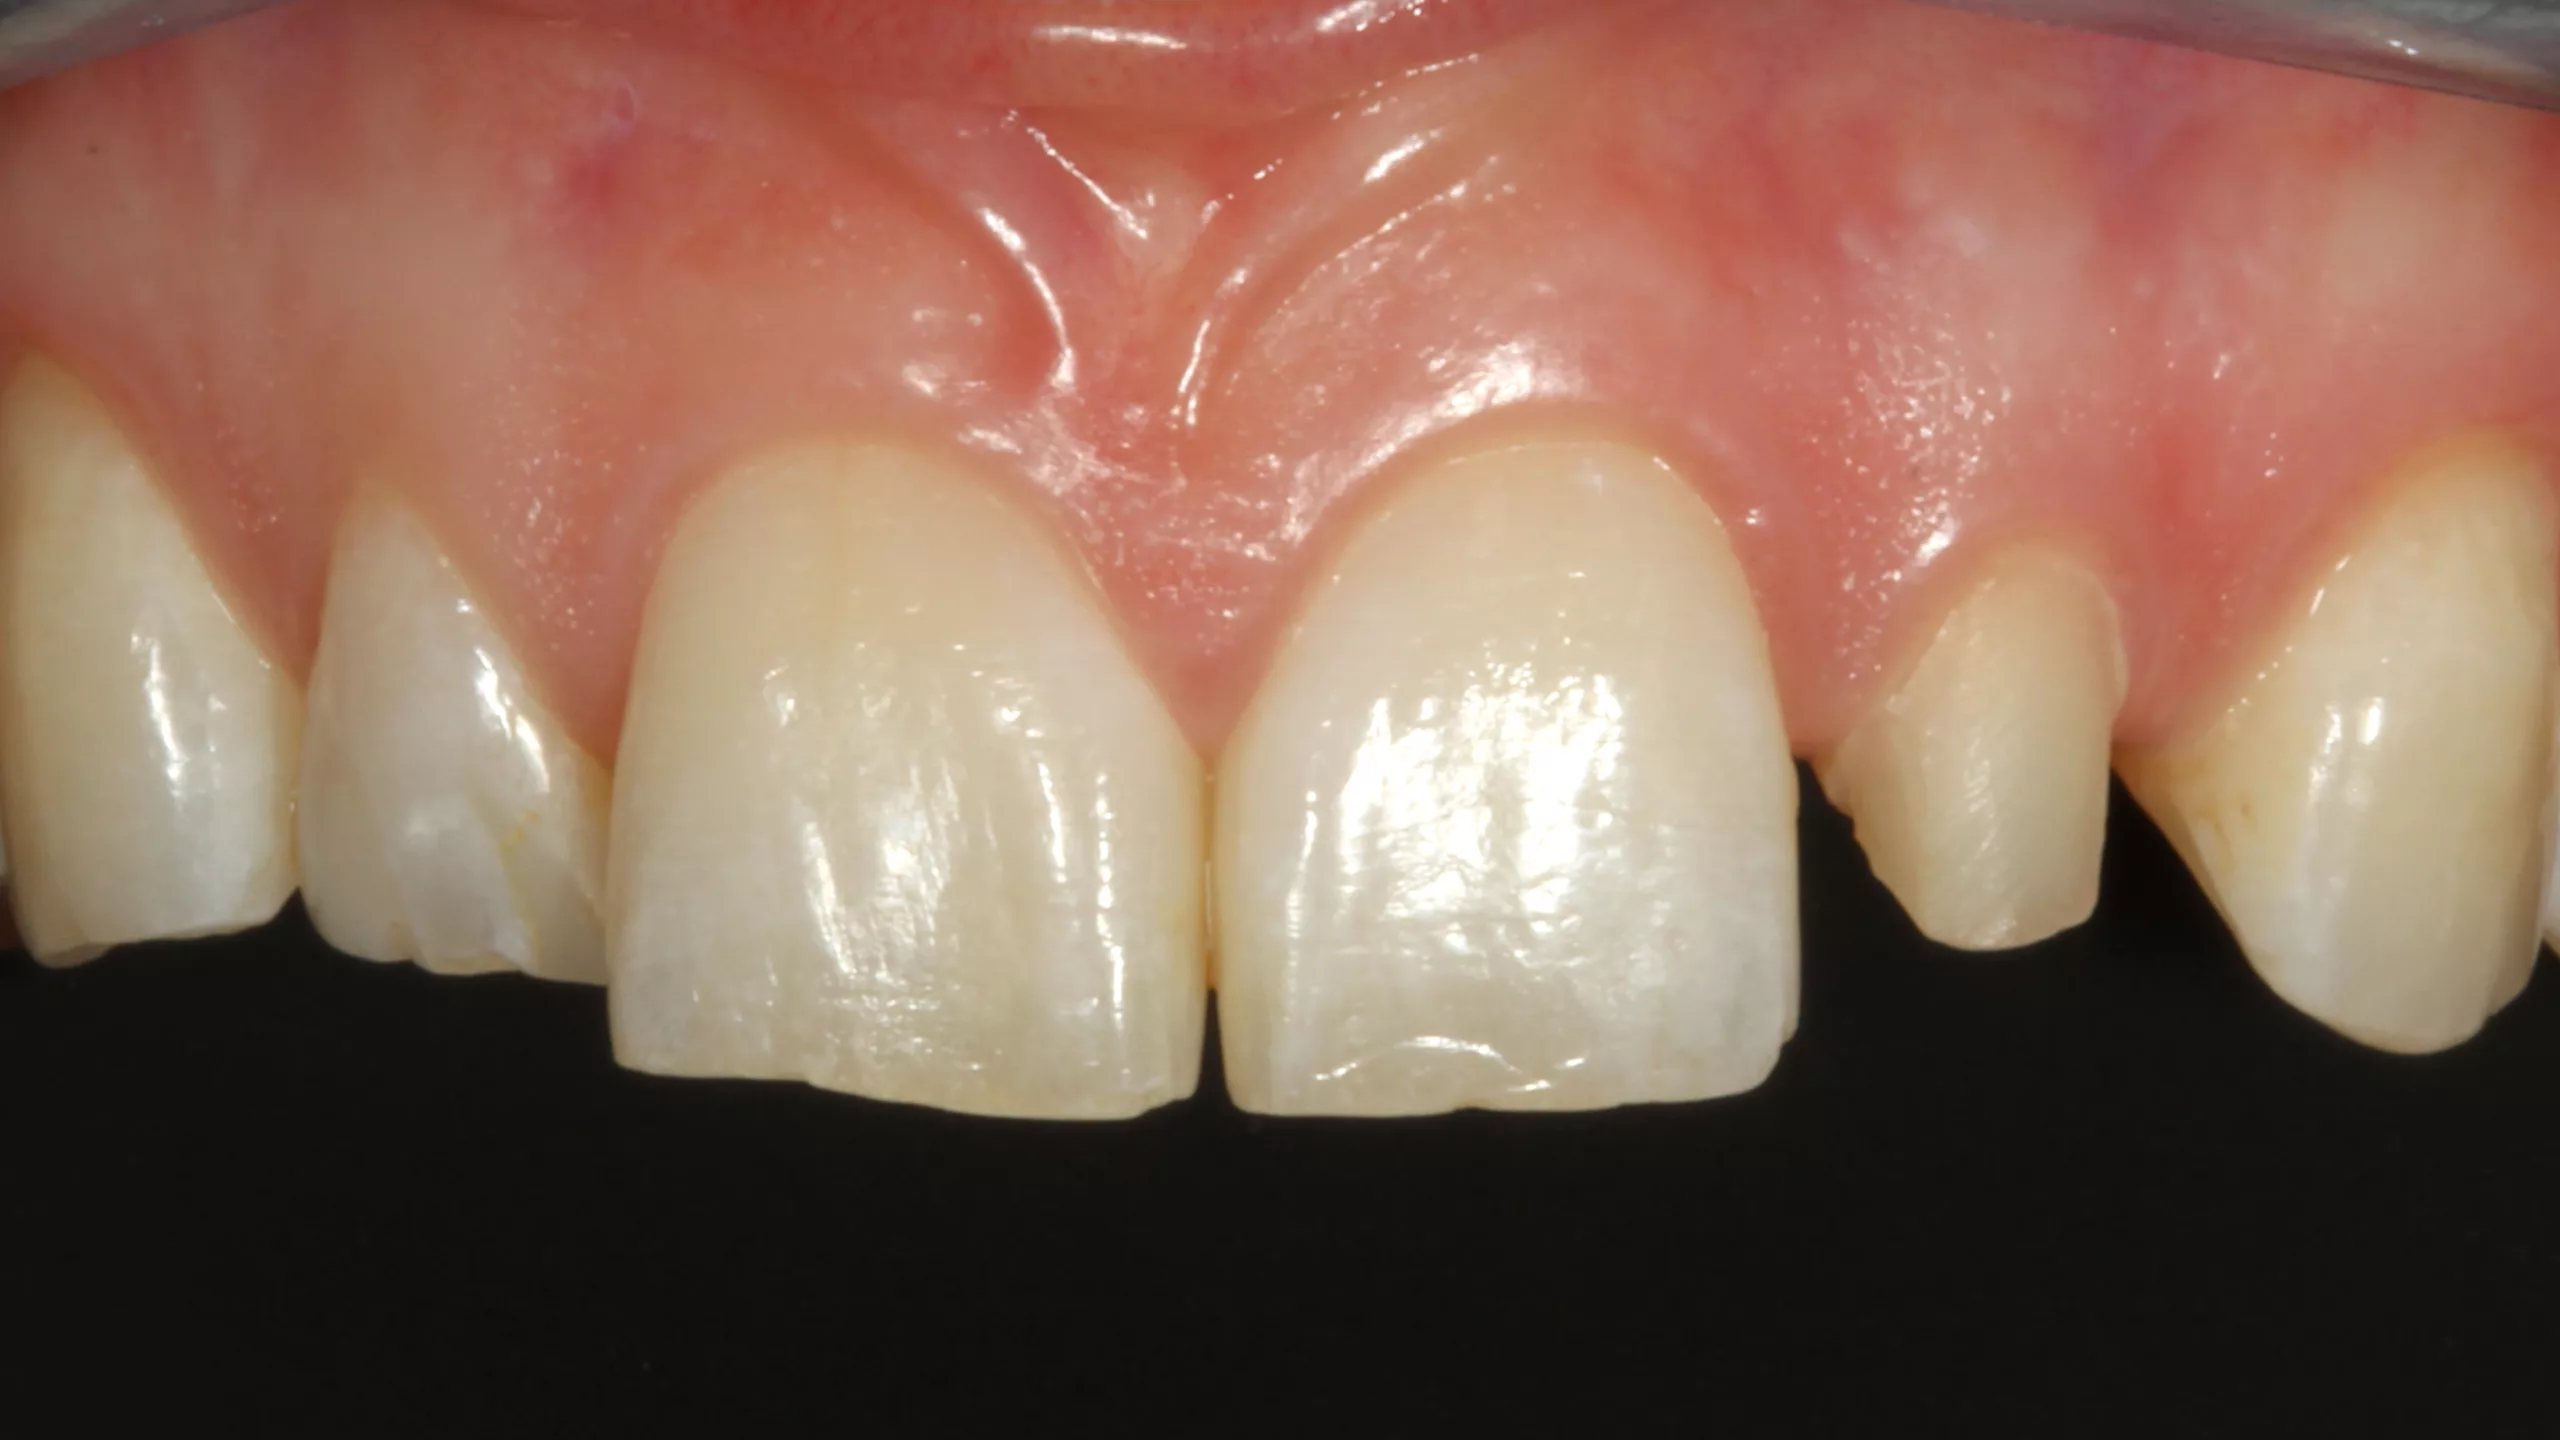

Die Abbildung 19 zeigt den bereits mit Kofferdam isolierten Zahn 22 nach der Reinigung der Oberfläche, die Abbildung 20 die Phosphorsäurekonditionierung der gesamten Klebefläche (Schmelz- und Dentinareale ließen sich nur schwer voneinander optisch differenzieren). Da der Visalys Tooth Primer auf mit phosphorsäuregeätztem Dentin genauso effizient funktioniert wie in seiner originären, selbstkonditionierenden Primerfunktion, sollte im Zweifelsfall besser großräumiger mit dem Phosphorsäuregel geätzt werden. Die Abbildung 21 zeigt den konditionierten Zahnstumpf aus inzisaler Sicht, die Abbildung 22 von labial. Wie in allen vorangegangenen Fällen erfolgte im nächsten Schritt die Applikation des Visalys Tooth Primers, dessen Einwirken für 20 Sek. (Abb. 23 und 24) und das Verblasen der Überstände bzw. die sorgfältige Evaporation des Lösungsmittels mit dem Luftbläser. Mit diesem Schritt war die Vorbehandlung des Zahnes abgeschlossen. Auch diese Krone wurde mit Visalys CemCore in der Farbe Universal (A2/A3) adhäsiv befestigt. Die vollständige Überschussentfernung erfolgte erneut mit einem sauberen Bondingpinsel (kein Microbrush) noch vor der Polymerisation (Abb. 25). Die Abbildung 26 zeigt die versäuberte, eingeklebte verblendete Vollzirkonkrone noch unter Kofferdam, die Abbildungen 27 und 28 das finale klinische Gesamtergebnis der sehr zufriedenen Patientin.